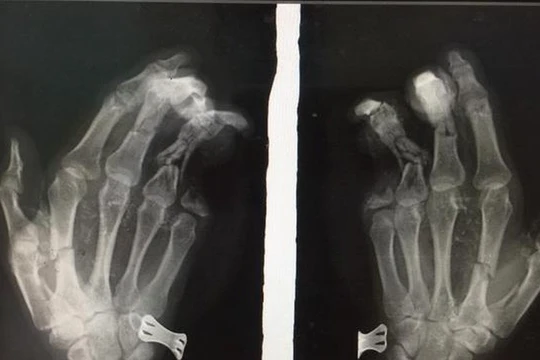

Khoảng 11 giờ 45 ngày 27/5, anh Lương Thanh Duy vừa sử dụng điện thoại di động vừa cắm sạc pin, chiếc điện thoại phát nổ khiến bàn tay trái của anh dập nát, tổn thương nặng và ngón út bị cụt 2 đốt.